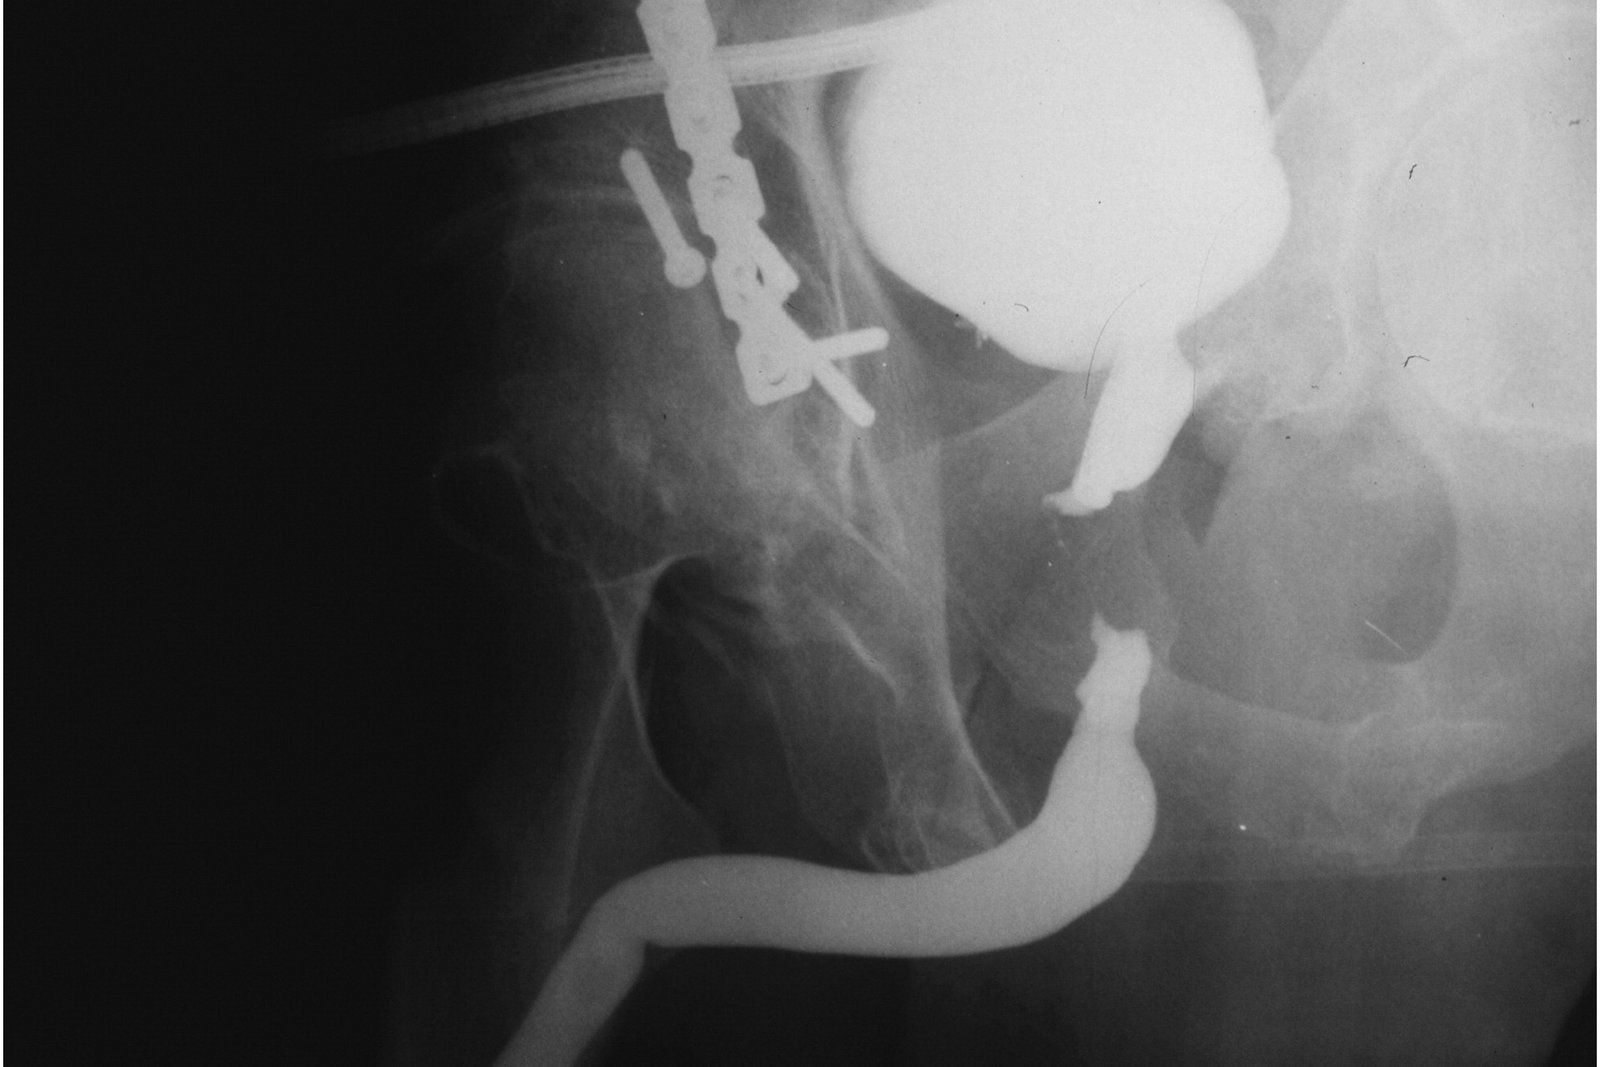

The procedure of stricture dilatation involves widening the narrowed area within the GI tract to restore normal function and alleviate symptoms. It is typically performed by gastroenterologists or interventional radiologists using specialized tools called dilators. The dilator is carefully inserted into the narrowed segment of the GI tract, such as the esophagus, stomach, or intestines, under imaging guidance to ensure precision.

There are different techniques for stricture dilatation, including balloon dilatation and bougie dilatation. Balloon dilatation involves using an inflatable balloon attached to the dilator. Once positioned at the stricture site, the balloon is inflated, exerting pressure to stretch and expand the narrowed area. Bougie dilatation, on the other hand, utilizes a cylindrical dilator (bougie) of varying sizes to gently stretch the stricture during the procedure.